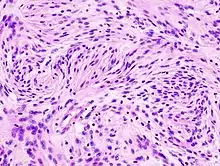

Astrocytomes anaplasiques

L'astrocytome anaplasique est une tumeur cérébrale maligne caractérisée par une croissance diffuse, une densité cellulaire accrue et des figures de division nucléaire. Elle est issue d'une population cellulaire spécifique du système nerveux central, les astrocytes. Selon la classification OMS des tumeurs du système nerveux central, la tumeur correspond à une tumeur de grade III.

En règle générale, les patients atteints d'astrocytome anaplasique présentent des crises d'épilepsie, des déficits neurologiques focaux, des maux de tête et des changements de personnalité. L'âge moyen des patients est de 45 ans. L'imagerie par résonance magnétique montre généralement une lésion massive avec un signal de contraste accru, qui peut aussi être plus faible. Le diagnostic repose sur l'examen histologique de la lésion par biopsie ou résection chirurgicale.

Un pronostic plus sombre peut être associé à un âge avancé, à une mauvaise condition physique et à des dommages neurologiques importants. En général, le résultat thérapeutique est meilleur avec une exérèse chirurgicale complète (traitement standard) sans augmentation des déficits neurologiques. La radiothérapie est la norme car il a été démontré qu'elle augmente le temps de survie. Le rôle de la chimiothérapie est controversé.